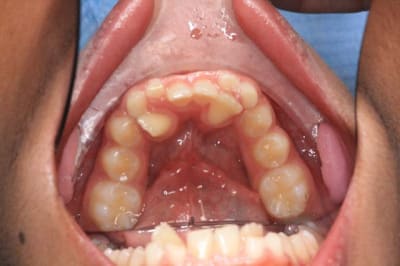

Voici un cas que l'on peut espérer stable

@+ Bjc.

Img 3374 ndr5wl - Eugenol

02/07/2013 à 21h11

Cher Algi,